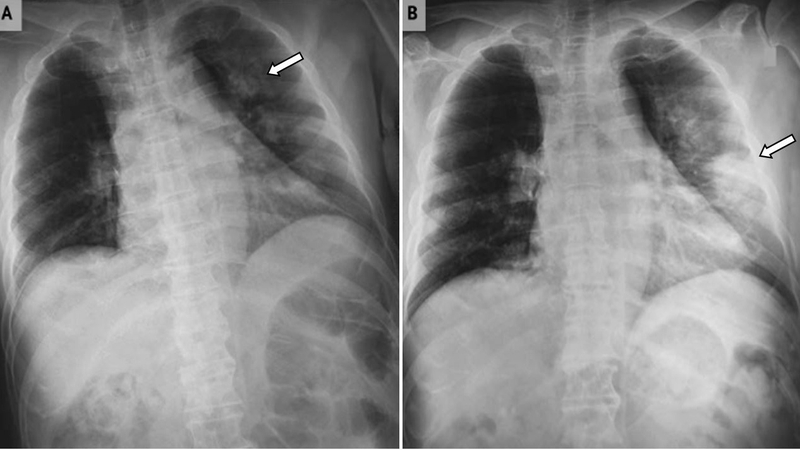

Phổi trắng không phải là một bệnh lý cụ thể mà là thuật ngữ dùng để mô tả hình ảnh X-quang khi các tổn thương lan rộng khắp phổi, khiến chúng xuất hiện màu trắng mờ trên phim chụp. Hiện tượng này là dấu hiệu của nhiều bệnh lý nghiêm trọng khác như viêm phổi cấp tính, bệnh bụi phổi nghề nghiệp, bệnh bụi amiăng…